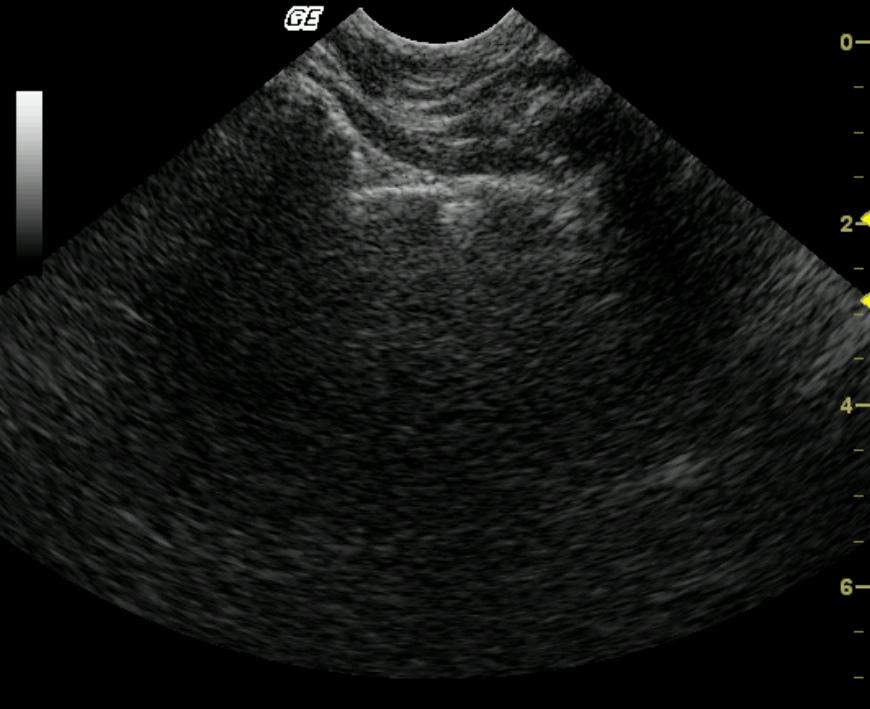

A 7-year-old MN DSH cat was presented for intermittent vomiting typified by vomiting 2-3 times a week. The patient also had a history of constipation. The physical exam revealed mild dehydration (estimated at 5%), pyrexia, a grade IV/VI heart murmur and large amounts of firm stool in the descending colon. CBC showed a neutrophilia. Blood chemistry showed elevated ALT and hyperamylasemia. T4 was within normal limits.